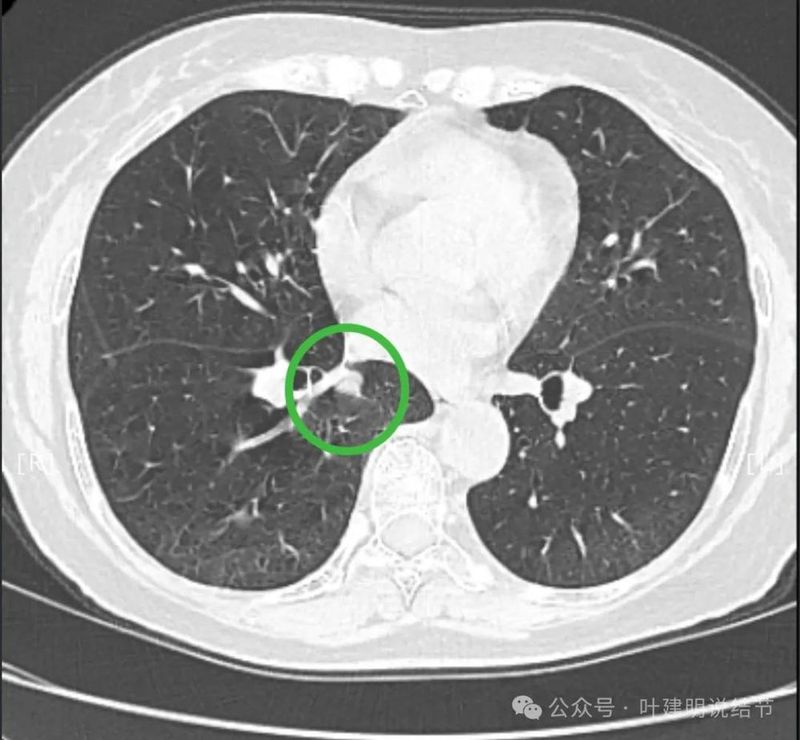

先看患者提供的2024年2月份的CT影像:

病灶出现,在右下叶支气管旁边,轮廓清楚,此层似磨玻璃密度。

表面似分叶状,密度不纯,邻近血管略有弯曲向病灶。

实性密度,边缘光滑,与背段支气管亚段贴着。